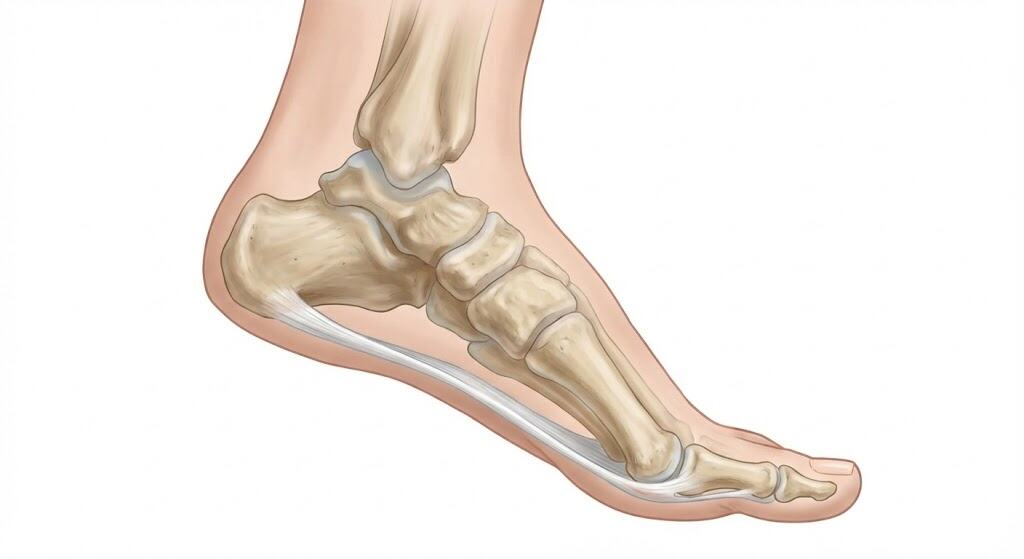

1. הכשל של Peroneus Longus (ייצוב דינמי)

- במצב תקין: השריר Peroneus Longus מתחבר לבסיס המסרק הראשון ומושך אותו כלפי מטה (Plantarflexion) והחוצה, ובכך "נועל" אותו כנגד הריצפה ומייצב אותו.

- בפרונציה (כף רגל שטוחה): עקב צניחת הקשת, זווית המשיכה של השריר משתנה. הוא מאבד את המנוף המכאני שלו ("Lever arm dysfunction").

- התוצאה: המסרק הראשון מתרומם (Dorsiflexion) והופך לבלתי יציב (Unstable First Ray). כעת הוא חופשי לנדוד פנימה (Medially).

2. אובדן מנגנון ה-Windlass

כאשר המסרק הראשון מתרומם, הפאסיה הפלנטרית לא נמתחת כראוי בזמן הליכה (Fail of Windlass Mechanism). הבוהן לא מצליחה לייצר דחיפה יעילה, והעומס עובר למסרקים הקטנים (2-4), מה שגורם למטטרסלגיה (כאבים בכריות) המלווה לעיתים קרובות הלוקס ואלגוס.